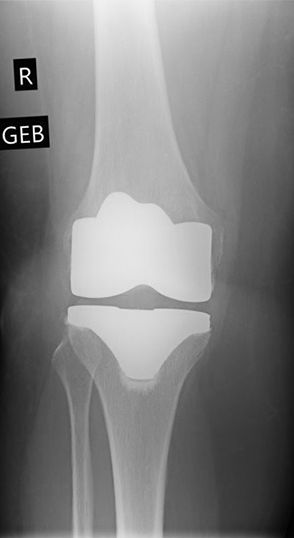

Oberflächenprothese eingepflanzt

Oberflächenersatzprothese

Sind am betroffenen Knie mehrere Gelenkanteile verschlissen und abgelaufen, kommt meist nur ein vollständiger Oberflächenersatz in Frage. Hierbei wird das Knie über einen Schnitt von ca. 10 - 12 cm geöffnet und der geschädigte Knorpel und Knochen oberflächlich, also in einer Schichtdicke von 2 - 4 mm abgesägt. Bei sehr guter Knochenqualität wird die Oberflächenprothese ohne Verwendung eines Knochenzementes verpresst. Durch die aufgeraute Oberfläche der Prothese zum Knochen hin, wächst dieser in die Prothese ein und verankert diese so stabil. Bei reduzierter Knochenqualität (meist ab 65 Jahren) wird eine feste Verbindung von Knochen und Prothese durch Knochenzement erreicht.